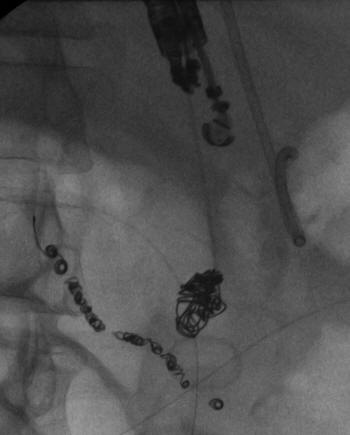

Transcatheter Coil Embolization Of An Arc Of Buhler Aneurysm

Coil embolization of Arc of Buhler aneurysm in 41-year-old man. A. Axial enhanced CT image shows 2 cm diameter aneurysm, which using Nester coils (Cook Inc., Bloomington, IN), and originating from the celiac axis to prevent reperfusion of the aneurysm sac. ... Retrieve Document